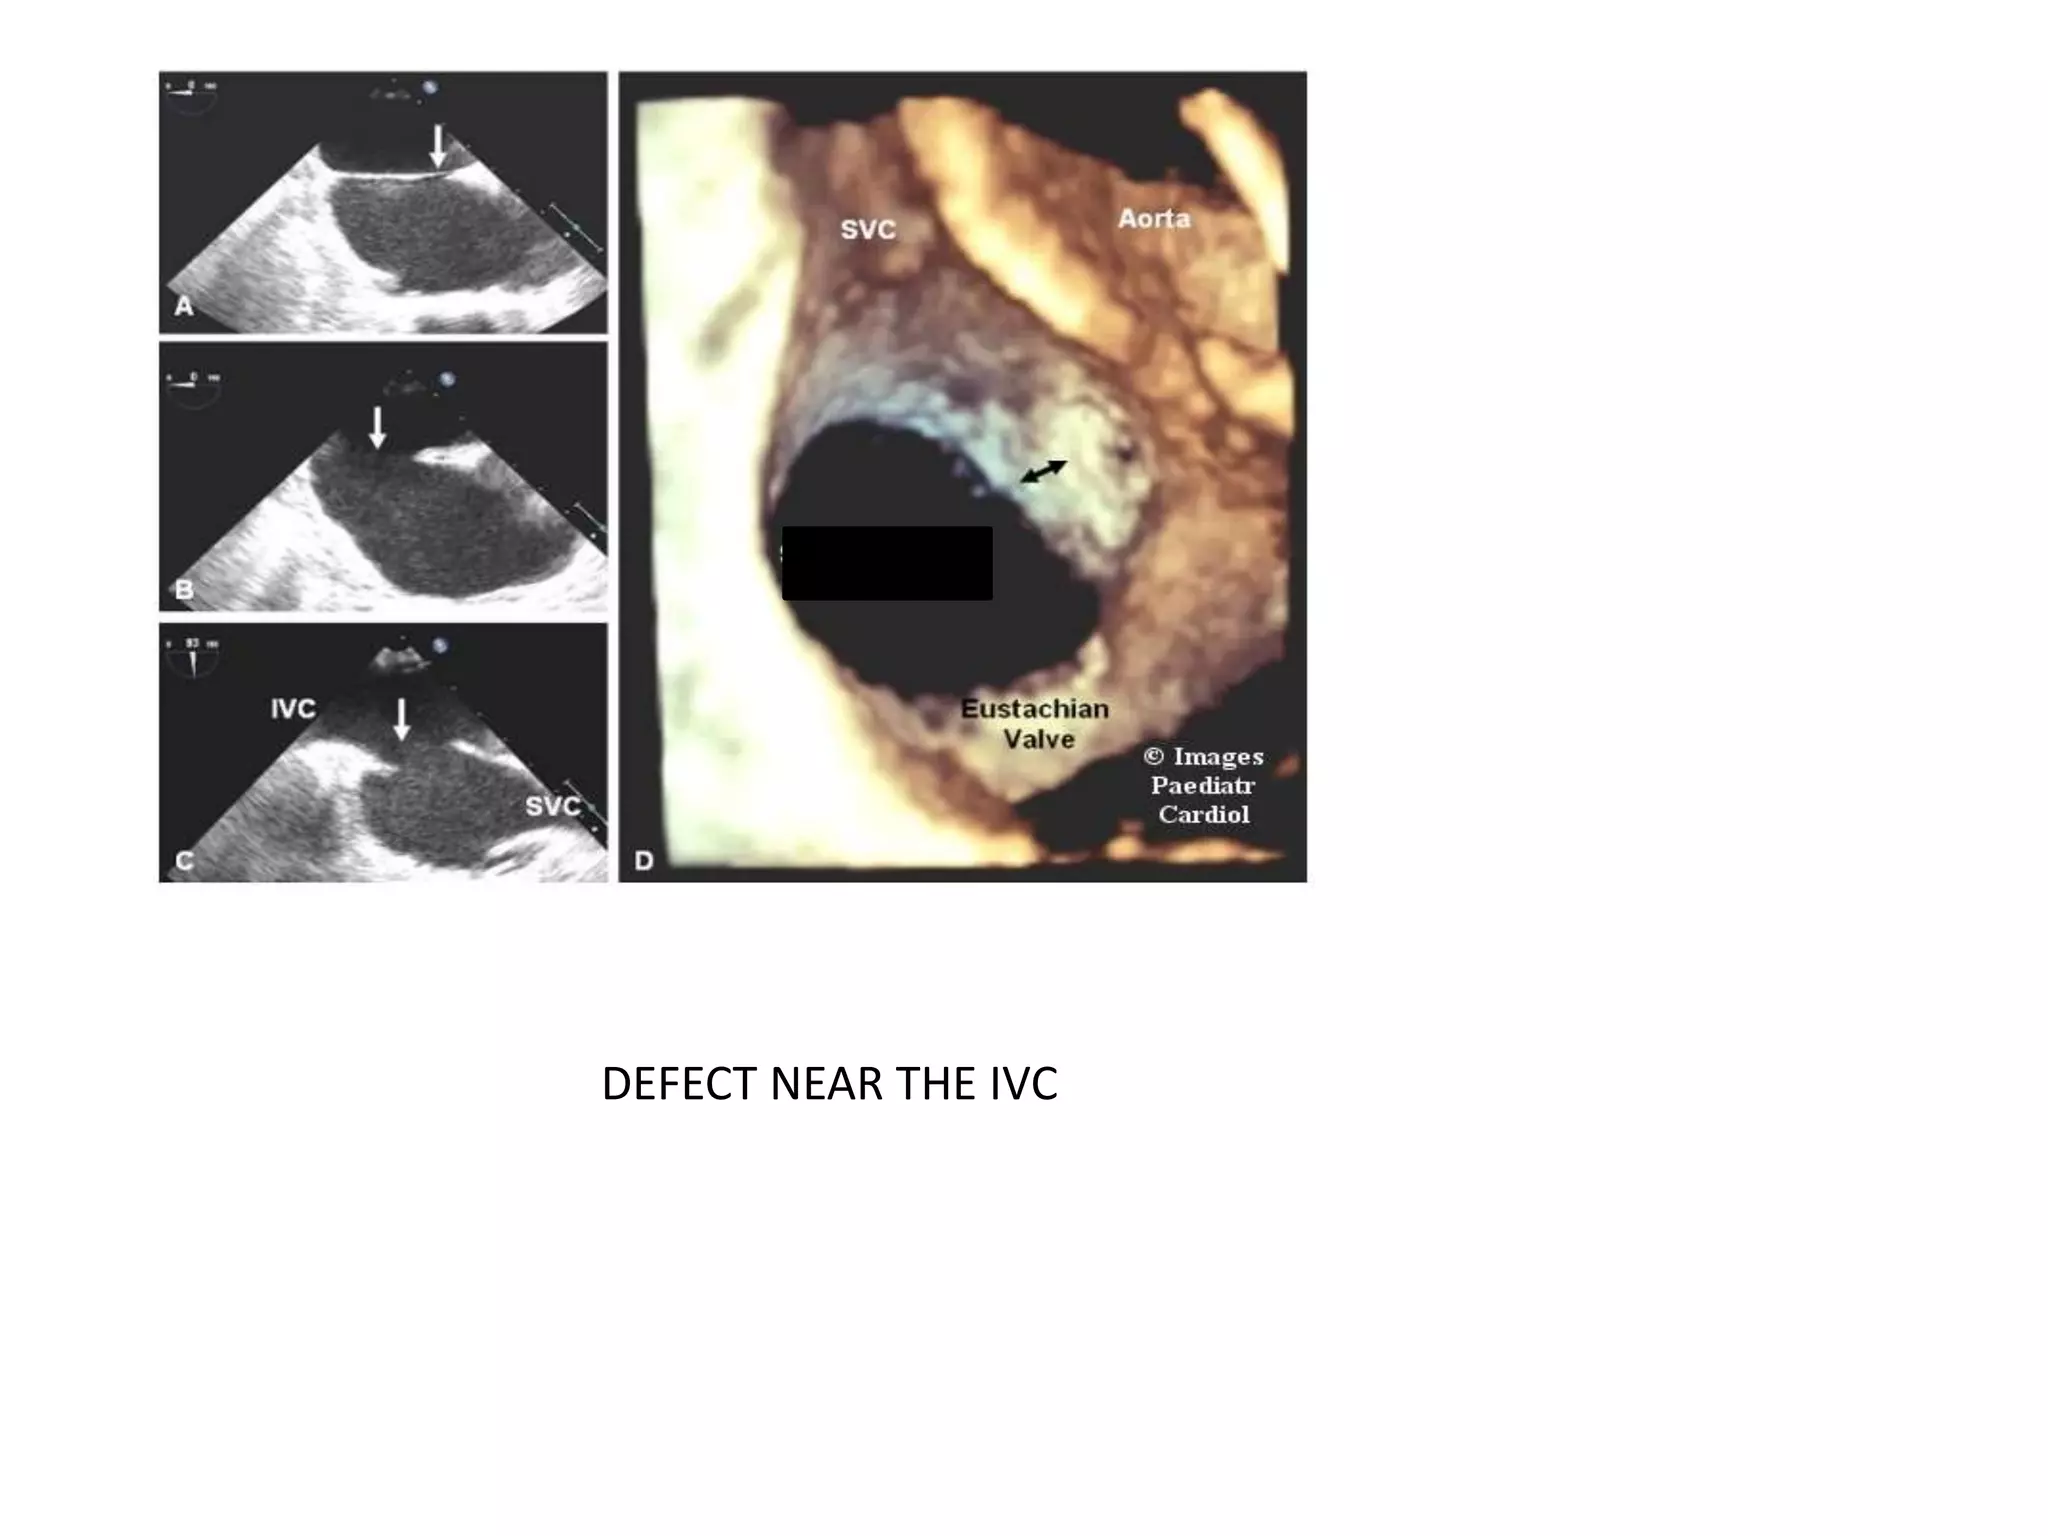

DEFECT NEAR THE IVC

3D echo- En face 3D reconstruction of a secundum ASD with

a relatively deficient

IVC and posterior rim